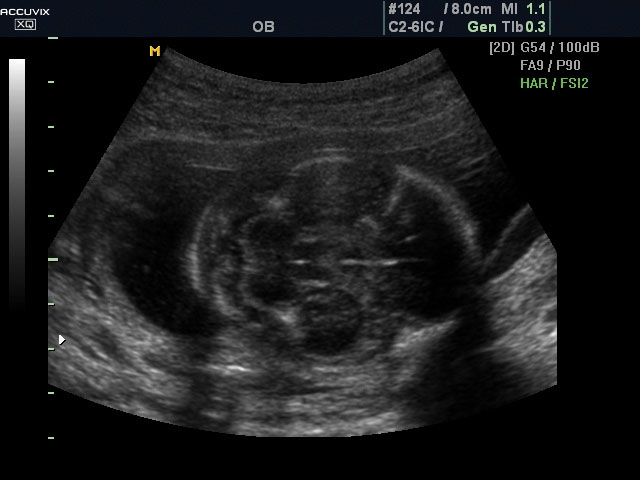

A pontos analízis és diagnózis iránti egyre növekvő igény kiszolgálására a MEDISON egy új real time képfeldolgozó technológiát fejlesztett ki Dynamic MR™ elnevezéssel. Az eljárás a diagnosztikus ismeretanyagot a precizitás és a pontosság egy teljesen új szintjére emeli. Használata az alapvető 2D ultrahang képinformáció real time, kivételesen kristálytiszta és kiemelkedően részletezett megjelenítését teszi lehetővé tűéles kontúrok és finoman rajzolt szövetstruktúra mellett. A DMR™ technológia ideális eszköze az ultrahang-diagnosztikának kezdve a szülészet-nőgyógyászattól a foetalis echon át az általános alkalmazásokig.

A DynamicMR alkalmazása az átlagos ultrahang teljesítményt a zaj és szemcsézettség jellegű műtermékek kiszűrése révén a vizuális diagnosztika, a precizitás és a pontosság új szférájába emeli. Figyelje meg a cerebellum, CSP és cisterna magna élstruktúráit, mennyire pontosan definiáltak és a teljes agyi struktúra ábrázolása a Dynamic MR alkalmazásával milyen látványosan javul.